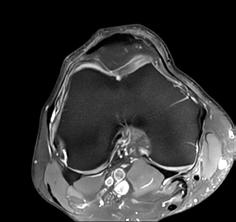

AiCE - High resolution imaging with short scan times

Ankle

16ch Flex SPEEDER, WFS (Water Fat Separation), AiCE, Res: 0.3 x 0.3 x 3 mm,

Scan time: 3:13 min.